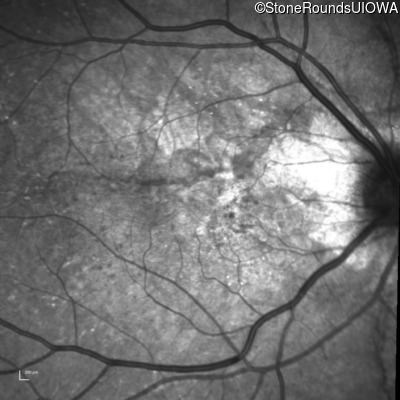

Infrared Fundus Photograph - Right - 20/20 -1

Exemplar